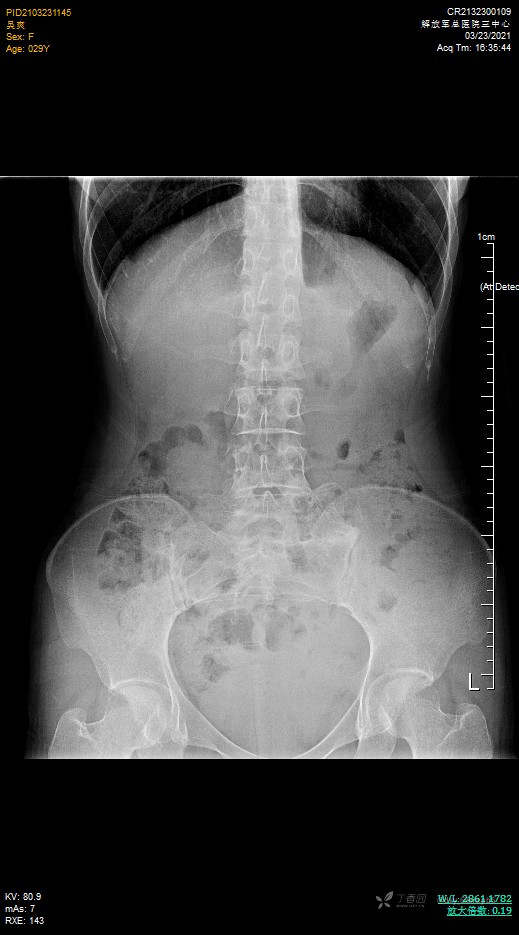

腹平片未见异常

2021-3-26平卧位,左下腹18#套管针穿刺,腹腔注气2000ml,人工气腹后腹部多体位平扫,GE图像工作站进行数据VR成像(腹膜腔三维成像):

平卧位:腹膜腔气腹空间完整,肝脾形态位置正常,结肠小肠肠管平面分布,管径大致形态正常。结肠内容物偏多,48小时口服显影线位于横结肠左半以远。子宫形态大小正常。

平卧位图:中下腹肠管平铺,未见腹壁粘连。